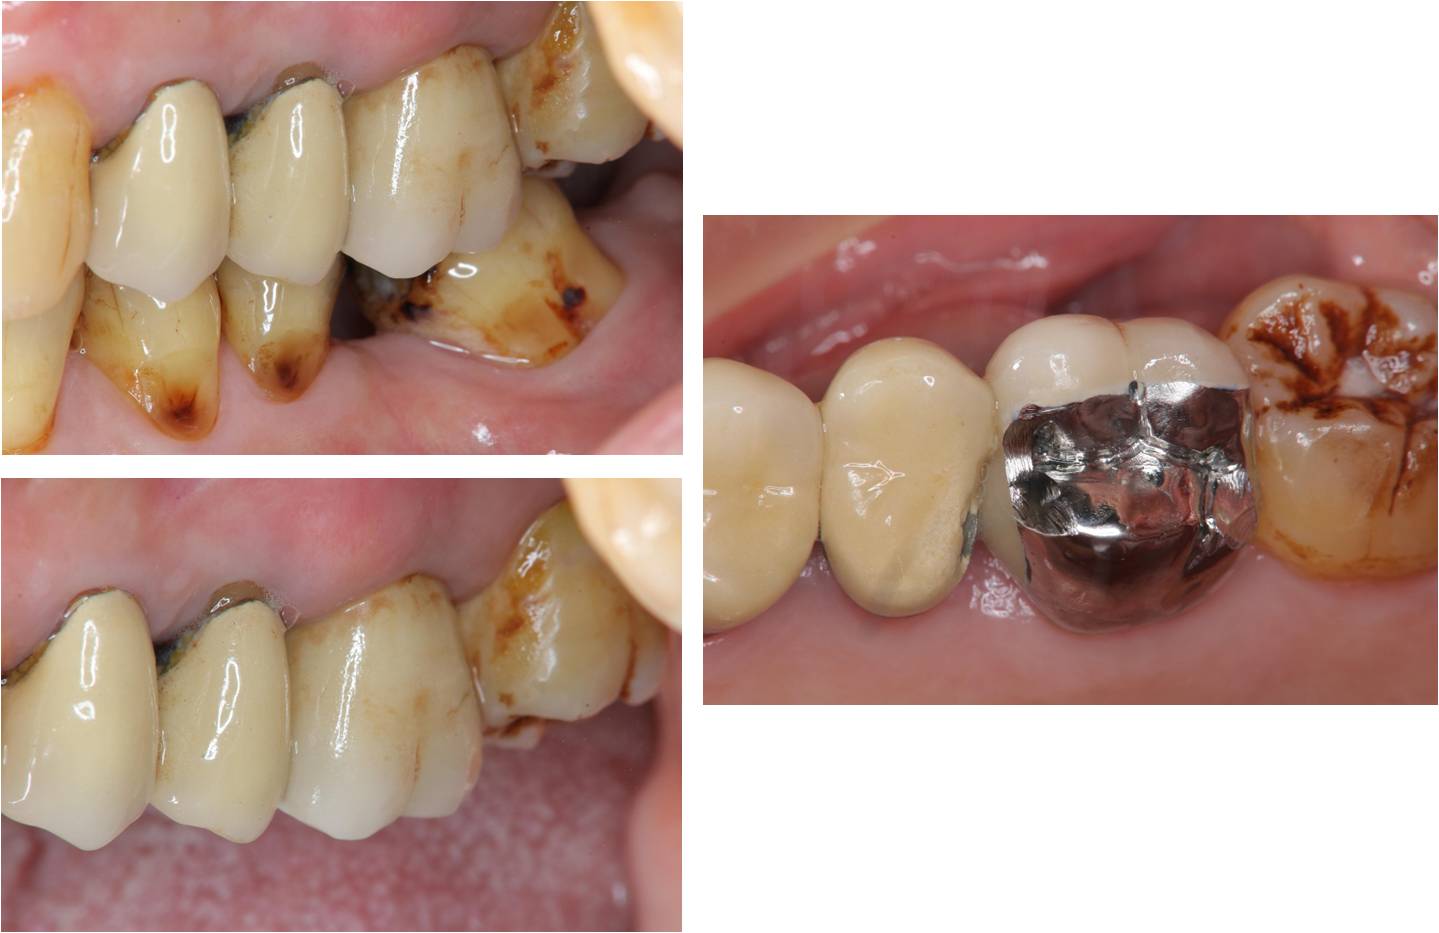

治療前,牙齦下蛀牙

蛀牙至牙髓

牙齒製備